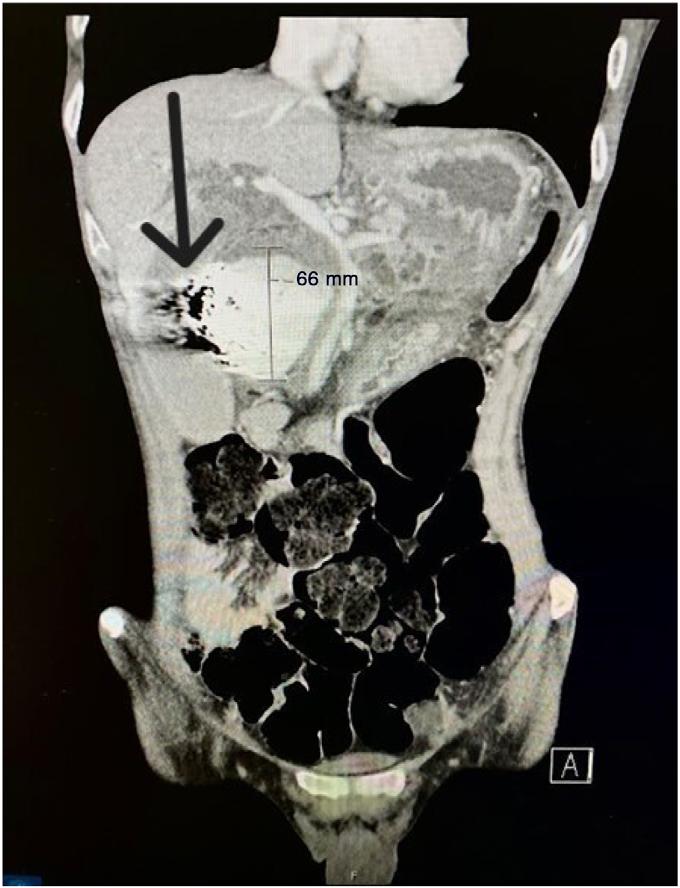

Image. Computedtomographyabdomenwithintravenouscontrast demonstratingdilated, fluid-filledloopsofsmallbowelandapattern ofswirlingmesentericvesselscalledthewhirlpoolsign(arrow).

Onpresentationthepatientwasinnoacutedistressbut wasclammyandtachycardicatarateof118beatsper minute.Onexam,herabdomenwasdiffuselytenderwithout distentionorperitonealsigns.Shehadanelevatedwhite bloodcellcountat17 × 103 permicroliter(K/μL)(reference range4.5–11.0K/μL),anINRof5.5,andalacticacidof 3.7millimolesperliter(mmol/L)(0.4–2.0mmol/L).An abdomenandpelvisCTwithintravenous(IV)contrast showed findingssuspiciousforclosedloop,smallbowel obstruction.TheCTalsodemonstratedevidenceofswirling ofthemesentericroot,knownasawhirlpoolsign(Image, Video).The findingsofthewhirlpoolsignonCTsuggested mesentericvolvulusasthecauseofherbowelobstructionand promptedemergentsurgicalconsultation.

pathology.However,radiographsareofteninconclusivein midgutvolvulusbecauseevenapositive “doublebubble” signindicatingasmallbowelobstructiondoesnotruleouta concomitantmidgutvolvulus.7 Computedtomographywith IVcontrastgivesmuchgreaterdetailoftheabdomenandcan provideevidencesuggestiveofamidgutvolvulus.ClassicCT imaging findingsincludeawhirlpoolsignoftwisted mesentery,malrotatedbowelconfiguration,inverted superiormesentericarteryandsuperiormesentericvein relationship,bowelobstruction,andfree fluid/freegasin advancedcases.8 ThewhirlpoolsignseenonCTrepresents themesenteryandsuperiormesentericveinwrapping aroundthesuperiormesentericarteryina counterclockwisedirection.